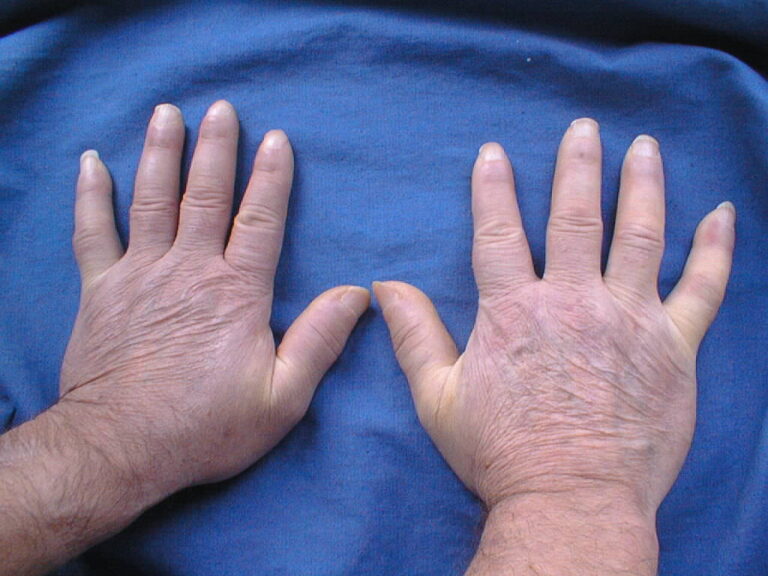

Na správnou diagnózu čekají lidé se sklerodermií roky

Poporodní deprese, lupus, hypochondrie. I tyto diagnózy si vyslechli pacienti, než u nich lékaři odhalili systémovou sklerodermii. Vyplývá to z dotazníku, který mezi nemocné rozeslala pacientská skupina Skleroderma Revma Liga Česká republika. Téměř 30 % z dotázaných si svoji skutečnou diagnózu vyslechlo až za 10 let od prvních příznaků nemoci. Roky tak prožili v nejistotě, […]